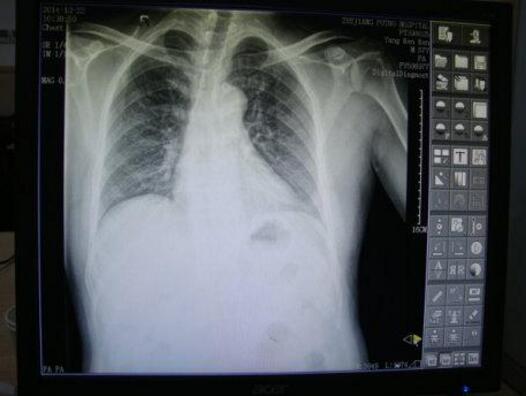

王怀庆主任根据李先生的症状,迅速为他制定了一套科学方案进行治疗,李先生来院复查,影像学等各项检查都显示其关节均已恢复正常,故其中期滑膜炎在我院临床康复。...[详细]